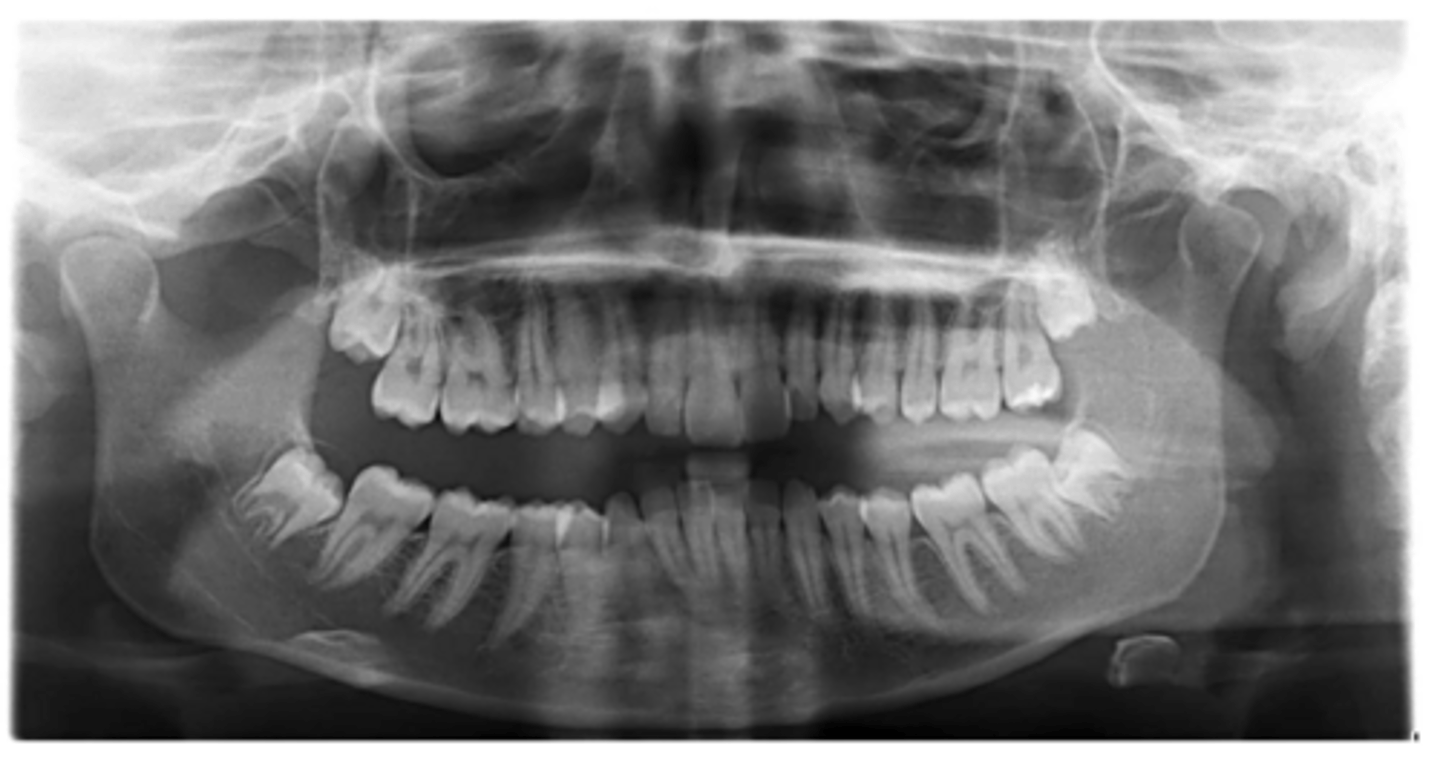

Premolar #13 (unerupted in pano) is more tilted than the opposing side (#4), which indicates an ectopic eruption pattern.

(Primary teeth w/o resorbing roots is also present)

What abnormalities/concerns do you see in this pano?

Third molars and mandibular right second premolar

Are there any congenitally missing teeth in the maxillary arch?

#29 (mandibular right second premolar)

Are there any congenitally missing teeth in the mandibular arch?

mandibular right second molar

Are there any retained primary teeth?

maxillary canines

Are there any impacted teeth?

Yes

Is there crowding?

More or less

Are the condyles symmetrical?

Maybe?

Is there any pathology?

Are there any ankylosed primary teeth?

No, just one in an odd position

Is there any ectopic eruption?

No

Are there supernumerary teeth?